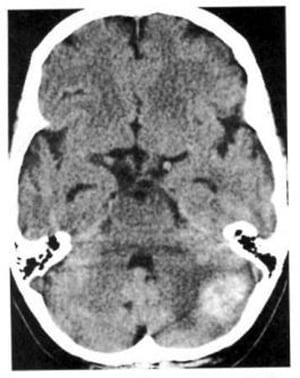

1.7. U thần kinh (u bao Schwann) (Hình 1.61, 1.62)

Dấu hiệu XQCTĐT:

– Rất thường xảy ra ở thần kinh thính giác và khu trú ở góc cầu tiểu não.

– Trừ khi hoại tử, nó thường có mật độ ngang và bắt chất cản quang rõ.

Chú giải:

– Trong bệnh u xơ thần kinh loại 2, hai u bao Schwann có thể nối tiếp nhau sau nhiều năm hoặc có thể xảy ra đồng thời.

Hình 1.62. U thần kinh thính giác hai bên bắt mạnh chất cản quang ở một bệnh nhân có bệnh u xơ thần kinh loại 2.